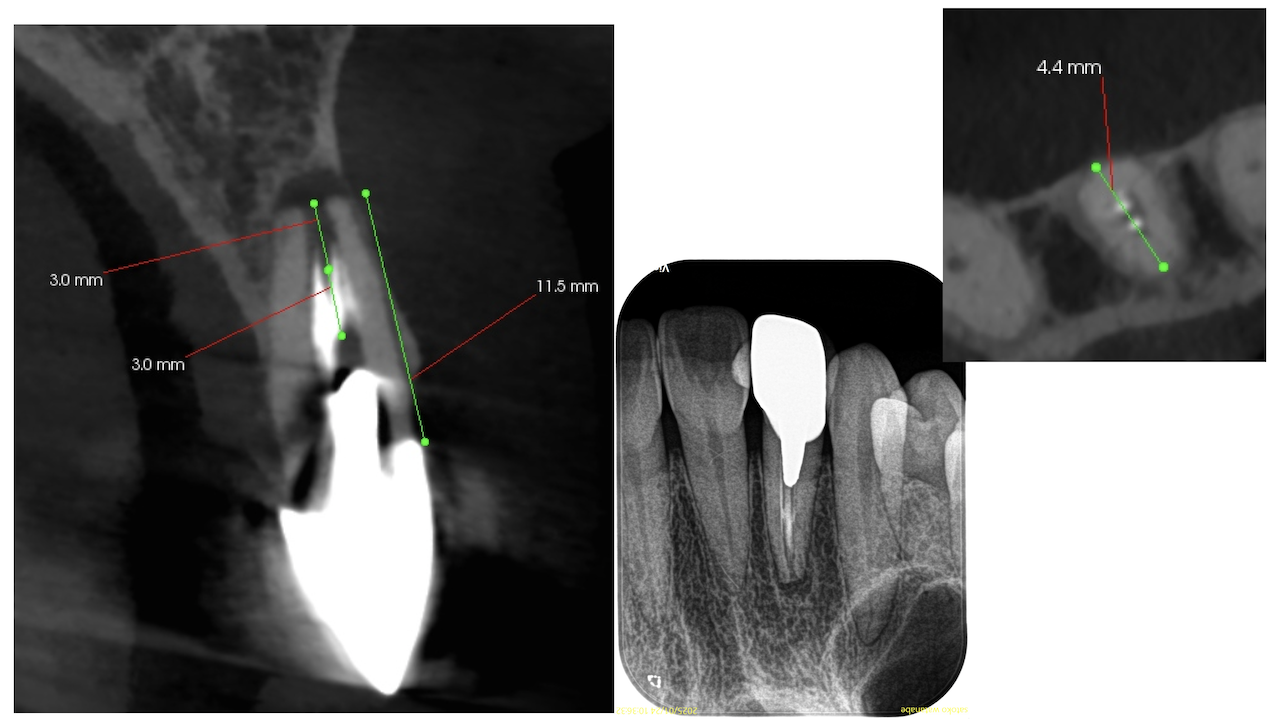

根尖が既に開いており、圧痛があったことから治療は再根管治療ではなく、歯根端切除術であるということがわかる。

その際は、

クラウンのマージンより11.5mm下方に#7のApexはあり、そこを3mm切断するには頬舌的に4.4mmの幅があるということがわかる。

実にEasyなApicoectomyだ。

また、治療の進め方は

外科治療の前にメタルポストコアを除去し、ファイバーポストコアに変更してから処置を行う

という方針を立てて行うことにした。